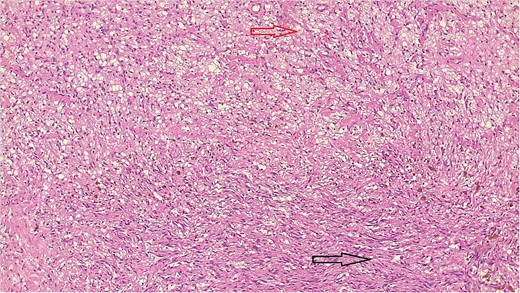

The result of the fine needle aspiration (FNAC) was a bland-looking spindle cell lesion, suggestive of a neural origin lesion like schwannoma. The patient was positioned in a supine position after she received general anesthesia. The face was turned to the opposite side of the tumor with a slight extension of the neck. An S-shaped incision was carried out in the front of the ear to the ear lobule, then it curved around the mastoid process posteriorly near the mastoid process and swung to the upper cervical creases smoothly. The cervical-facial skin flap was elevated with dissection to expose the tumor adequately, and then a traction suture was placed over the earlobe to widen the visual field for the operator. Dissection was carried out until the tumor was completely exposed, showing a smooth, ovoid, and whitish mass along the main trunk of the facial nerve (Fig. 1). The nerve was seen entering and exiting the posterior aspect of the mass on both sides. The layers over the mass were opened, and the mass was enucleated, leaving a flattened nerve posteriorly. No parotid gland excision was carried out. The postoperative histopathological examination revealed neurofibroma (Fig. 2) with a positive expression for S100 immune stain (Fig. 3). Postoperatively, the patient developed moderate (grade III) facial nerve dysfunction with obvious but not disfiguring deformity of the right side of the face, likely due to the pressure effect of the mass or traction during the operation. Two months after the operation, the facial nerve status improved to grade one, and after 4 months, she developed full recovery of facial nerve function.

Bland-looking cellular spindle cells (dark arrow) infiltrating into adjacent fibrofatty tissue (yellow arrow), Hematoxylin, and Eosin stain. Microscopic power 4 × 10.